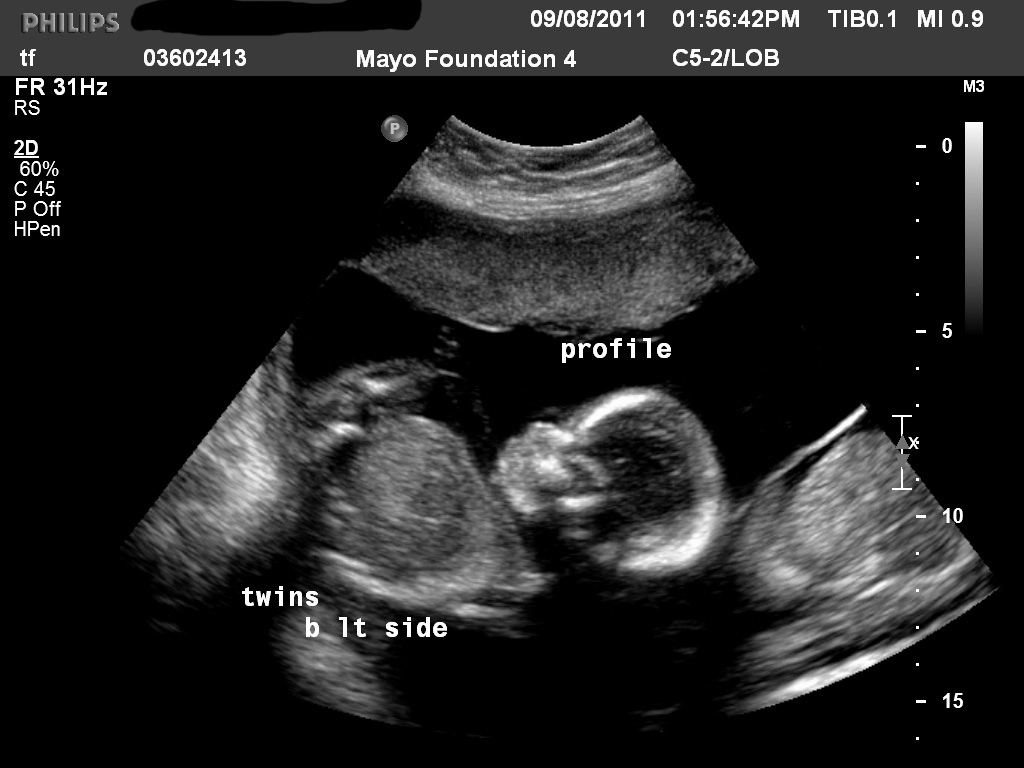

This is probably my favorite u/s pic. I love how the babies are resting their heads together.